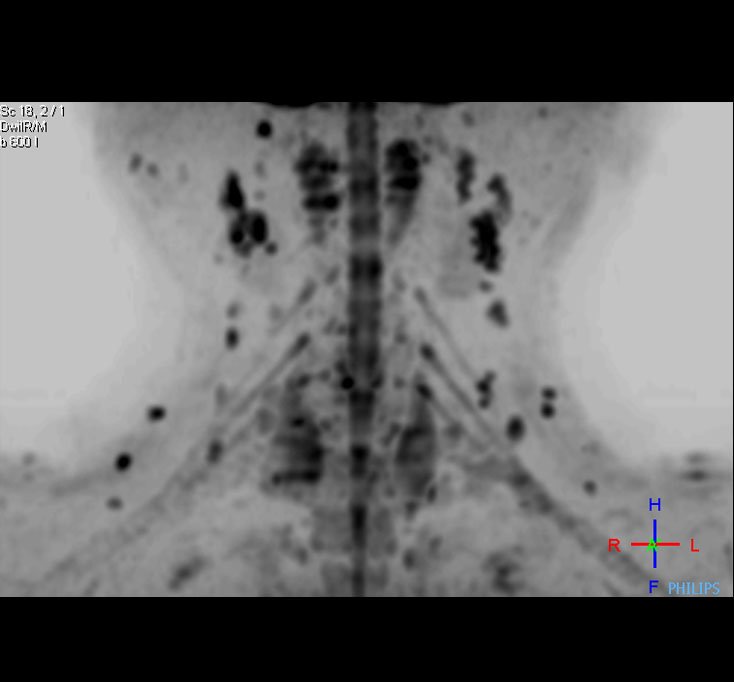

DWIBS ( Diffusion Weighted imaging with background suppression ) equivalent to PET MRI for metastasis screening (1st time in Gujarat )

DWIBS for Cancer Detection